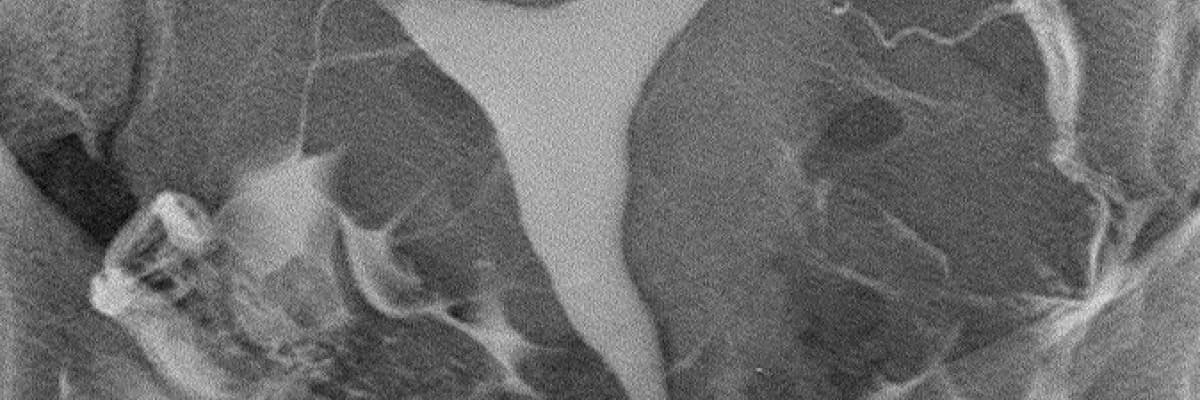

HSG (rahim filmi) incelemesi 50 seneden uzun süredir bilinmekte ve uygulanmaktadır. Buna karşılık son 20 yılda pek çok teknolojik ilerleme olmuş, buna uygun aparatlar üretilmiş ve yeni teknikler geliştirilmiştir. Söz konusu yenilikler şu başlıklar altında toplanabilir:

1-Dijital röntgen cihazları

2-C kollu dijital röntgen cihazları

3-Film banyosu ihtiyacını ortadan kaldıran termal veya lazer film baskı cihazları

4-Görüntülerin hekimlere bilgisayar ortamında gönderilmesini ve arşivlenebilmesini sağlayan dijital teknolojiler

5-Alerji riski düşük, yağ embolisi ve granülom oluşturma riski bulunmayan, osmolaritesi, viskositesi düzenlenmiş yeni nesil suda çözünebilir iyotlu kontrast maddeler

6-Kontrast maddeyi rahim boşluğuna veya doğrudan tüplerin içine doldurabilmek için geliştirilen ince, yumuşak, ucu balonlu veya balonsuz kateterler.

Bütün bu yenilikler, ağrısız rahim filmi çekimini mümkün kılmakla kalmamış, olumsuz yan etkiler çok azalmış, bazı komplikasyonlar ortadan kalkmış, gerek uygulamayı yapan hekimlerin gerekse hastaların maruz kaldığı radyasyon miktarları belirgin derecede düşmüş, film kalitesi yükselmiş, doğru teşhiş oranı yükselmiş, inceleme sayılarının artmasıyla birlikte birim maliyetler ve fiyatlar göreceli olarak düşmüştür. Yeni tekniklerin oldukça yüklü yatırım maliyetinin olmasına rağmen bir paradoks olarak eski teknik kullanılarak yapılan standart incelemelerin toplam birim maliyeti yeni tekniklerden daha ucuz olamamaktadır.

Sonuç olarak, rahim filmi çekimi için C kollu dijital röntgen cihazı bulunan ve yukarıda sayılan yeni teknikleri kullanan merkezler tercih edilmelidir.